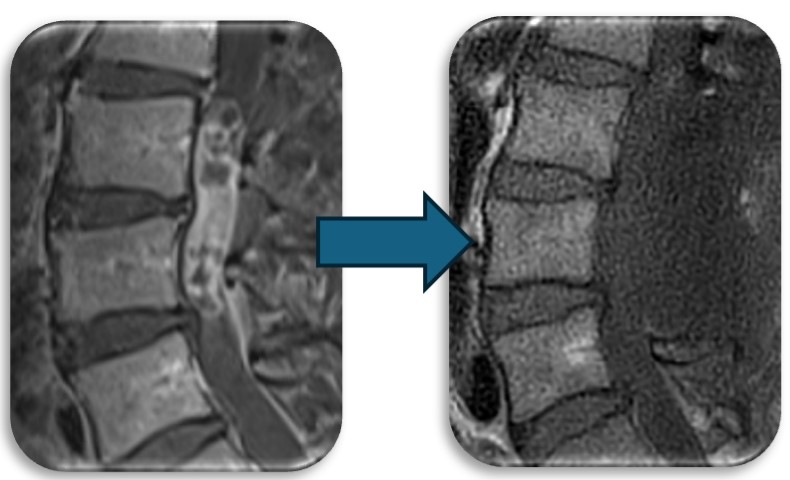

(代表例②)

腰部の脊柱管狭窄症に対して、腰の後ろから手術する椎弓切除術を行なった症例です。脊柱管と呼ばれる脊髄が通るトンネルの屋根部分にあたる椎弓を切除(点線部分)することによって狭かった脊柱管を広げます。